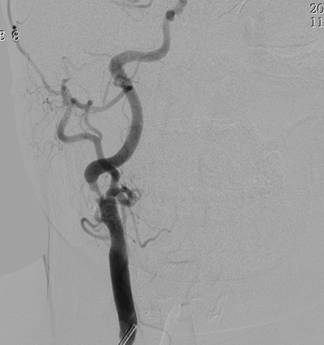

1周前,郭大姐再次发生右侧肢体无力的症状,于是家人将她送到广东三九脑科医院神经内科就诊,入院后积极完善相关检查,颅脑DWI显示:1、左侧基底节区、大脑脚及桥脑右侧、右侧枕叶多发陈旧性脑梗塞,2、考虑胼胝体压部偏左侧脑梗塞(偏慢性期)(如图1、图2)。DSA检查提示:1. 基底动脉末端闭塞,双侧大脑后动脉、后交通动脉未见显影,双侧大脑中动脉经皮层软膜动脉向同侧枕叶代偿供血;2. 双侧颈内动脉起始部重度狭窄(如图4、图5),狭窄率约90%,狭窄长度约20px;3.双侧椎动脉起始部中度狭窄,狭窄率约50%;4. 脑动脉硬化,颅内动脉走行僵硬,呈不同程度狭窄。

图 5 术前DSA提示:右侧颈内动脉起始部放大;